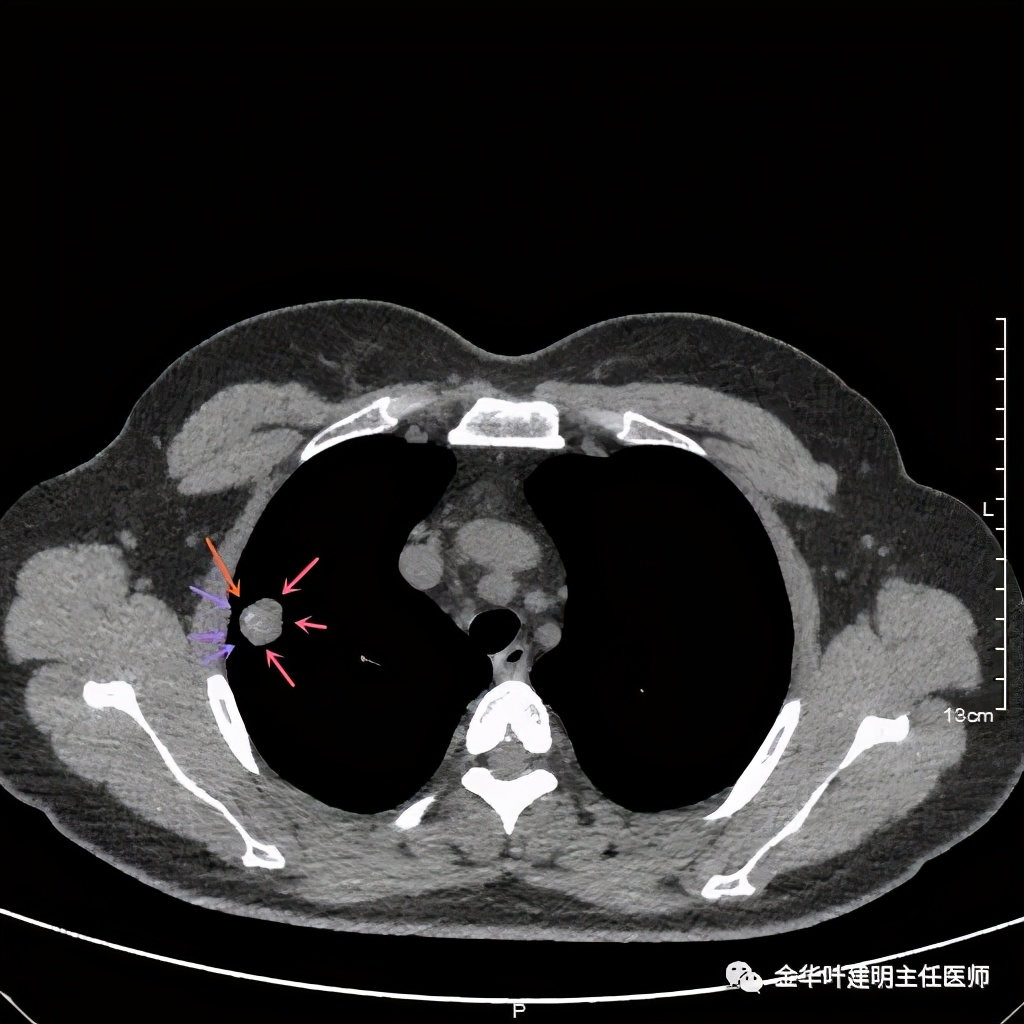

粉色箭头示病灶边缘光滑,没有毛刺,距胸膜近,但无牵拉凹陷。桔色箭头示病灶内有局部强化(血管?)

上图粉色箭头示病灶一侧非常靠边的地方居然有个小空泡:是结节内坏死形成的吗?这样大小的不符合呀,而且太靠边上了;是扩张的支气管吗?有可能,若病灶是肺癌,应该有破坏才比较符合,我们看它空泡比较光滑,没有堵塞或破坏。就是说,感觉与恶性是不太符合的。所以它应该是个良性的病灶!当然直径达2厘米的实性病灶,又这么靠外周部位,楔切非常简单,既可去除病灶,又可明确诊断,手术是可以考虑的。下面是术后病理结果: